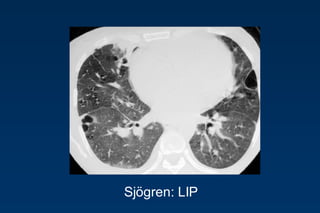

Benign lymphoproliferative disorder

Diffuse interstitial infiltration of

mononuclear cells

Not limited to the air ways as

in follicular Bronchiolitis

LIP

= Lymphocytic Interstitial Pneumonia

Sjögren: LIP

Rarely idiopathic

In association with:

Sjögren‟s syndrome

Immune deficiency syndromes, AIDS

Primary biliary cirrhosis

Multicentric Castlemean‟s disease